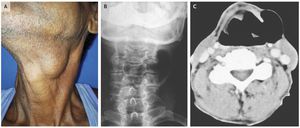

A 58-year-old man presented to the otorhinolaryngology outpatient clinic with a 2-year history of progressive hoarseness and swelling on the left side of his neck. He had no associated dysphagia, regurgitation of food, or dyspnea. He worked as a farmer and had no history of tobacco use. On physical examination, he had nontender, compressible swelling in the left cervical region that transmitted light on transillumination (Panel A). The swelling was accentuated when the Valsalva maneuver was performed (Video 1). Examination with a flexible fiberoptic laryngoscope showed a bulge over the left false vocal cord that was partially obstructing the airway lumen (Video 2). A diagnosis of laryngocele was confirmed by radiography of the neck (Panel B) and by computed tomography (Panel C), both of which showed a well-defined lobulated structure located in the left paralaryngeal space and extending through the thyrohyoid membrane. A laryngocele is a dilatation of the laryngeal saccule within the sinus of Morgagni, the space between false and true vocal cords. It can result from activity that increases intralaryngeal pressure, such as excessive coughing, straining, playing a wind instrument, or glass blowing. The patient underwent a complete excision of the laryngocele. He remained asymptomatic at a follow-up visit 8 months later. Chirom A. Singh, M.S. Pirabu Sakthivel, M.S., D.N.B., E.N.T., M.Ch. All India Institute of Medical Sciences, New Delhi, India source: nejm.org